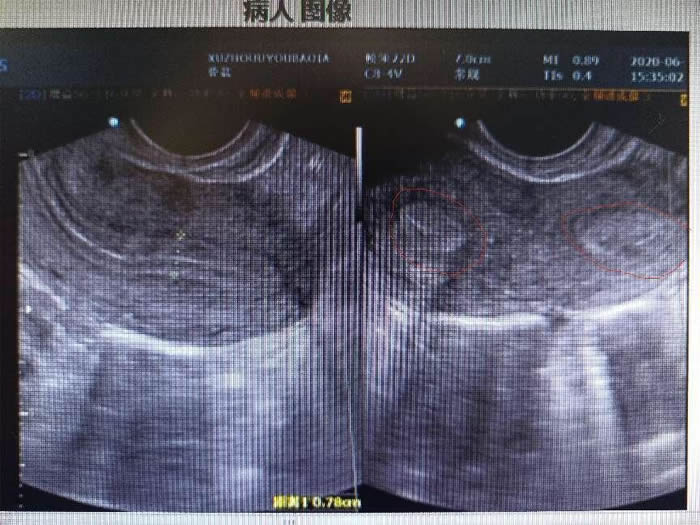

一年前,陳女士因為結(jié)婚兩年(nián)未(wèi)孕、痛(tòng)經(jīng)嚴重來到醫院就診。彩超檢查後發現(xiàn)陳女士子(zǐ)宮畸形,單角子宮合並殘(cán)角子宮II型,殘角子宮有功能(néng)內膜,與(yǔ)單角子宮宮腔不相通,每次(cì)月經經血逆流導(dǎo)致陳女士腹(fù)痛難忍,日常還伴(bàn)有同房的性交痛。